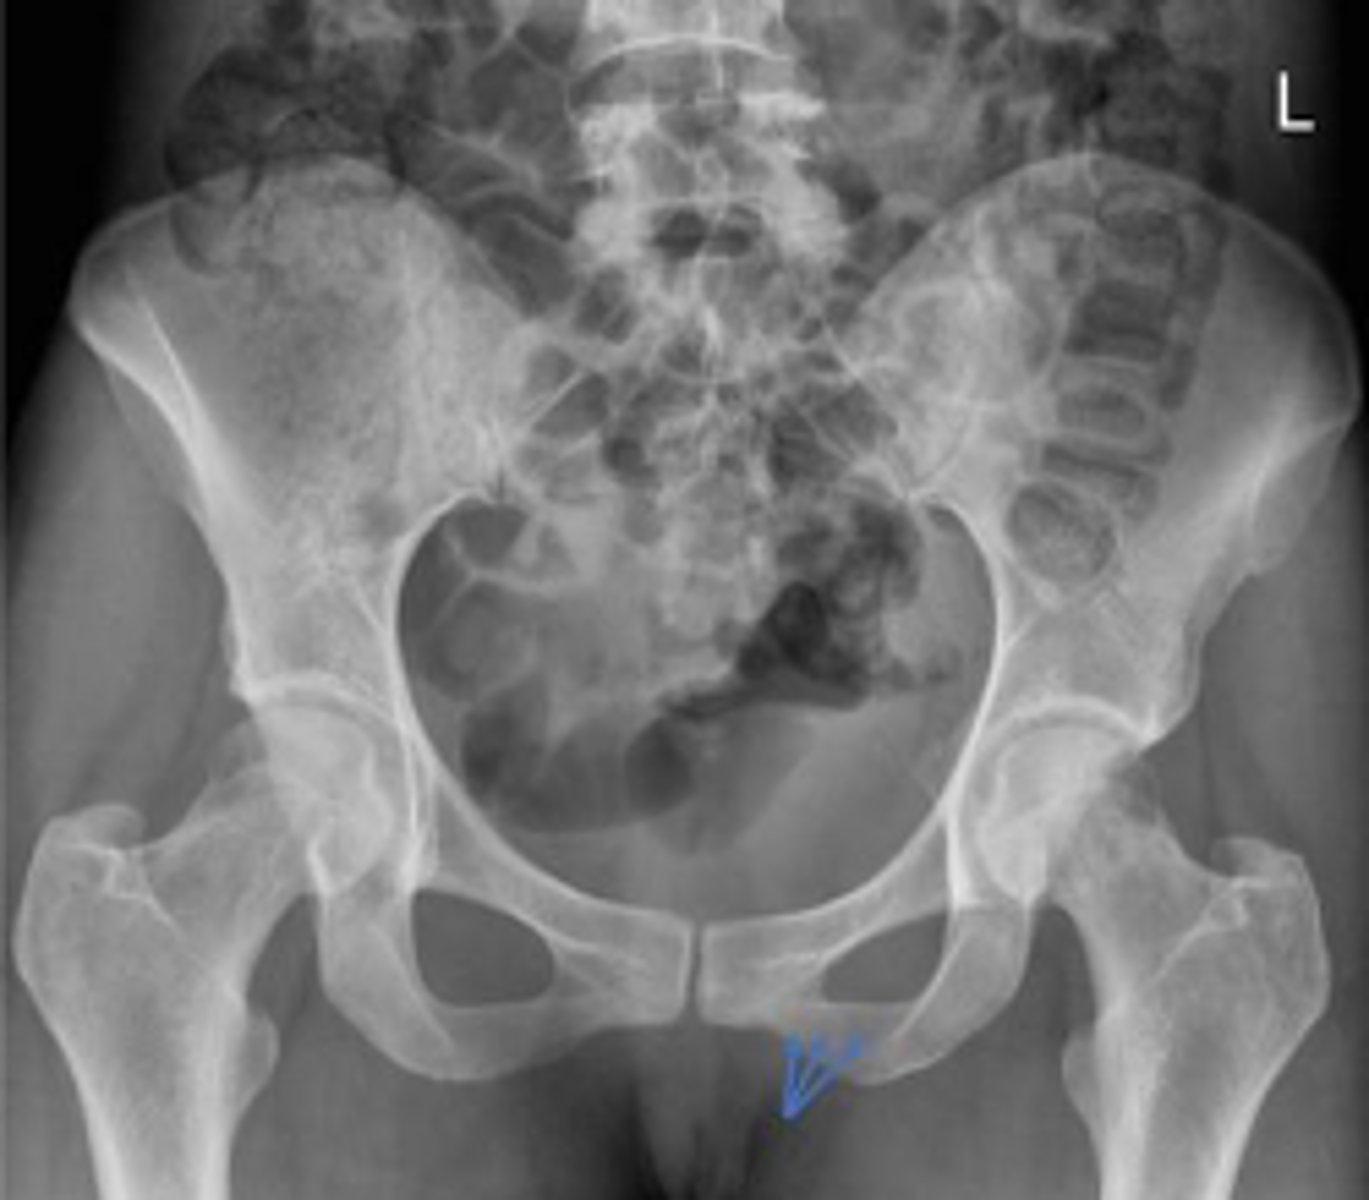

Bilateral frog leg view

What is the name of the radiographic view?

Phleboliths

What are the arrows pointing to?